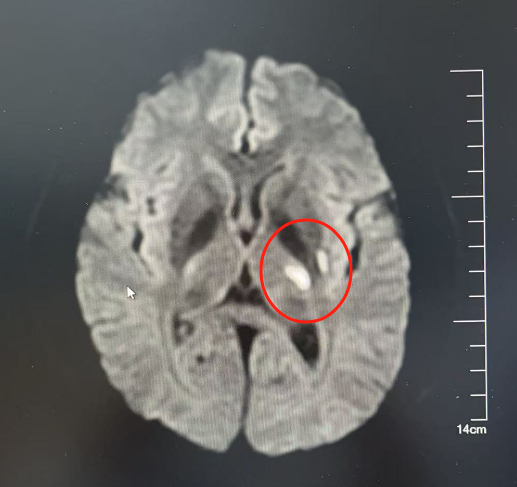

CT检查考虑是动脉粥样硬化导致的急性脑梗死(俗称:中风)。

小张的影像学检查结果